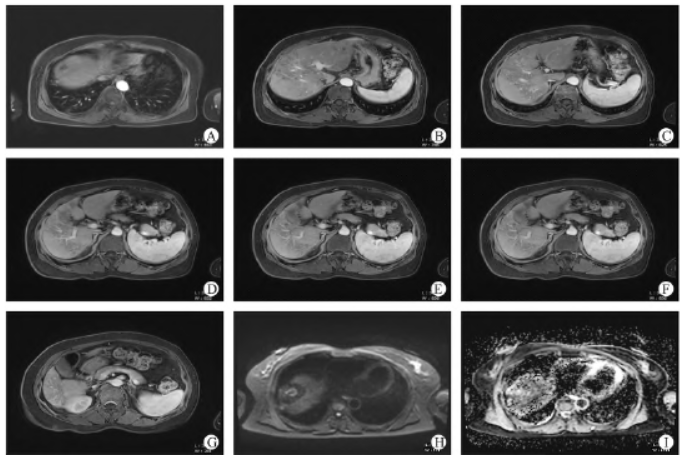

患者女性,53 岁,在体检时发现肝内多发结节(约14个),较大者位于肝右叶S8 段,大小约4.2 cm × 5.2 cm ×2.9 cm,多考虑肝癌;肝左叶囊肿(图1)。肿瘤标志物示:AFP 415 IU/mL。行超声引导下肝脏肿物穿刺活检术,穿刺病检示:(肝肿物穿刺活检组织)肝细胞癌,中分化(图2)。

图2 病理图片A - C:经皮肝脏穿刺示:肝细胞高度异常增生癌变,癌组织呈实性、巢状或排列呈肝索样结构,细胞大,胞质丰富,界限不清,核大小形态不一,部分核巨大,畸形怪状,核膜厚,染色质颗粒粗,核仁明显,病理性核分裂象多见,间质血管丰富(A:HE × 100、B:HE × 200、C:HE × 400)。

免疫组化结果显示:CD34(血管+),Glypican - 3(+),Hepatocyte(+),Ki - 67(index 约5%),CK8 /18(+),CK19(-),CK7(-)。高敏乙型肝炎病毒脱氧核糖核酸定量检测:182IU/mL。根据CSCO 指南,对于Ⅱ期的肝细胞肝癌首选TACE治疗,现患者及家属无肝动脉介入治疗意愿,想用碳离子放疗治疗。临床诊断肝恶性肿瘤;cT2N0M0Ⅱ期;BCLC 分期:B(中期);CNLC 分期:Ⅱb期;Child - Pugh 分级:A 级;KPS 评分:90 分;慢性乙型病毒性肝炎